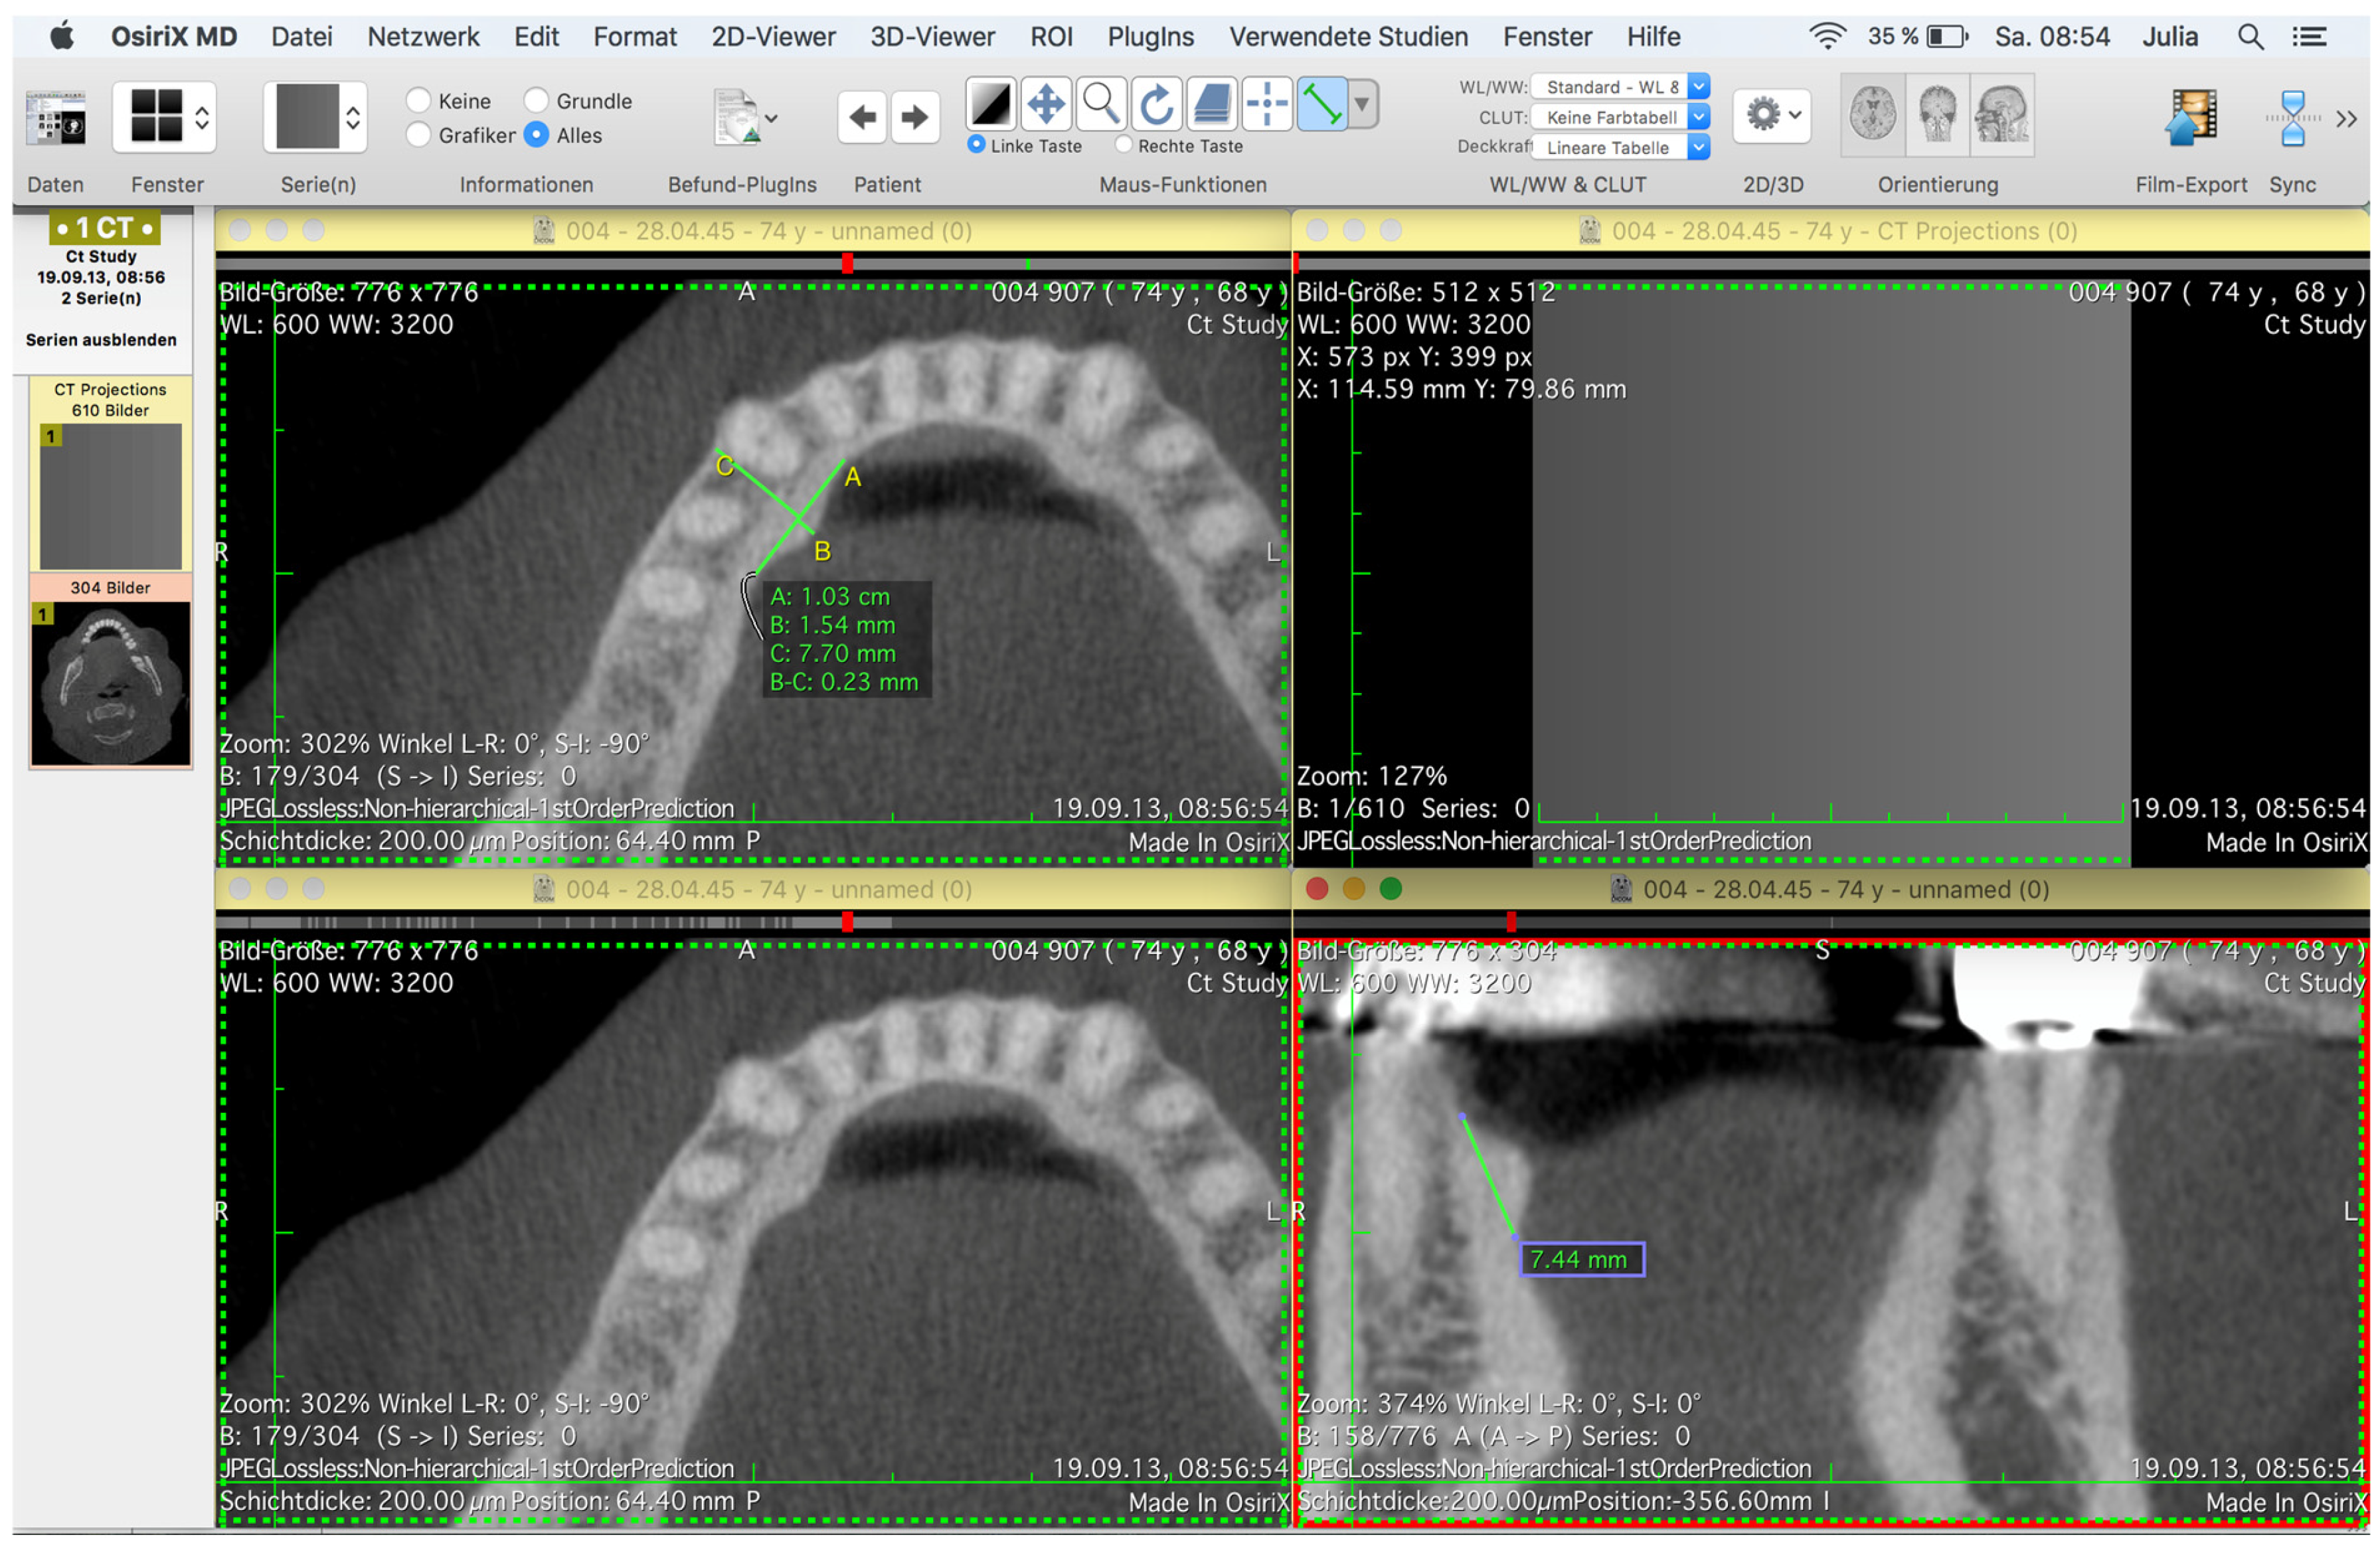

To find the maximum extension of a torus mandibularis, the lingual cortical bone was tracked under dynamic observation, and the maximum extension was determined again in each plane.

The first step was to find the plane in which the structure to be examined had its maximum axial extension.

The maximum extension of a torus mandibularis in the sagittal direction was marked by drawing a tangent line A; starting from this straight line, an orthogonal line B was drawn through a TM in its maximum transversal extension (Figure 2).

The straight line in question was extended to the mandible’s vestibular cortex, and a straight line was inserted from there to the mental foramen to obtain the distance between a TM and the mental foramen (Figure 3) and, thus, a conclusion about the localization of the TM.

The maximum vertical extension of the base was determined using the frontal (coronal) view. By dynamically viewing a TM in the frontal view, the maximum extension was again found, and a straight line was drawn through it (Figure 2 and Figure 3).

Figure 2. Data set of digital volume tomography, opened in OsiriX MD for measuring a left torus mandibularis in the axial and frontal planes. In the upper left window, line A shows the maximum extension in the sagittal direction, and line B shows the maximum extension in the transversal direction. Line C is the extension of B to the mandible’s vestibular cortex, from which the distance to the mental foramen was measured. In the lower right window, the green line shows the maximum extension of the TM in the vertical direction.